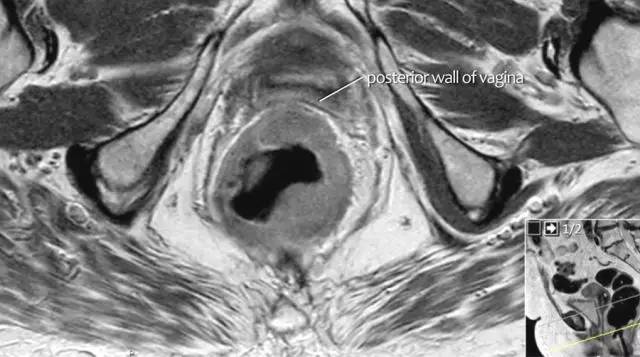

T4b 分期,侵入周围器官

T4 期肿瘤侵犯周围结构,如盆壁、阴道、前列腺、膀胱或精囊,这类局部晚期患者需要进行长程放化疗和广泛切除。

图 16 在矢状 T2W 图像上,直肠和阴道后壁之间有脂肪平面的损失。在轴向图像上,看到肿瘤的相对低的信号强度延伸到阴道的后壁(箭头)

以下 5 幅图例请连续观看:

图 17~21 肿瘤的低信号强度延伸到阴道的后壁(箭头)